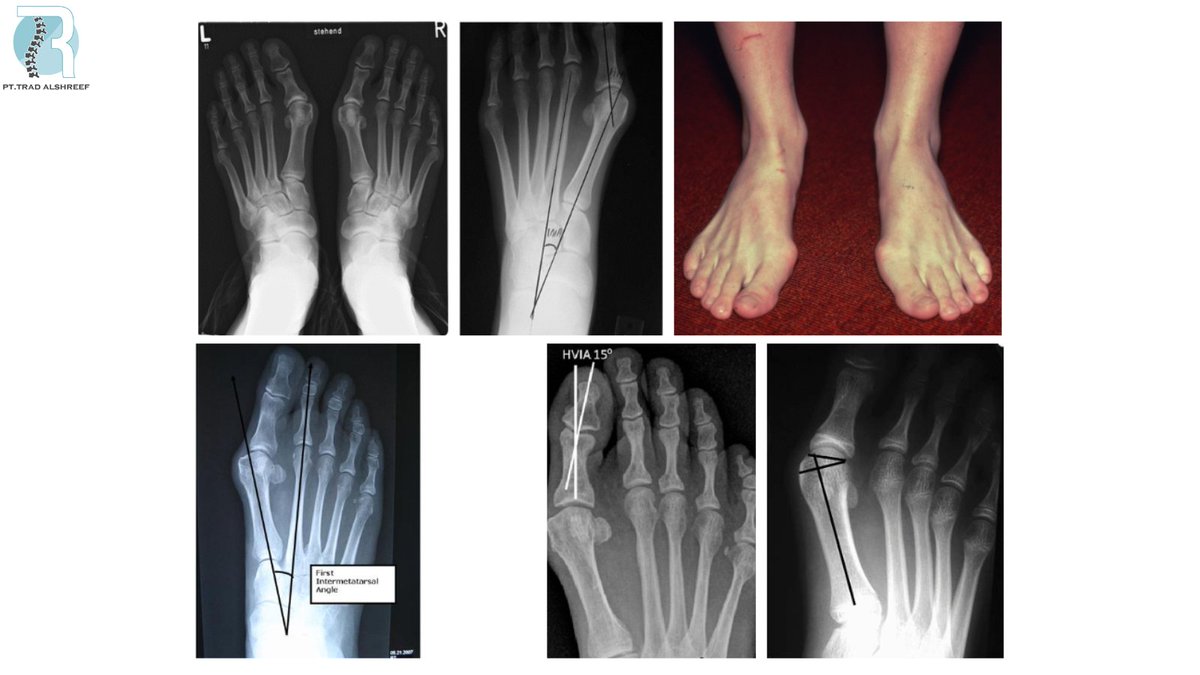

طريقة التشخيص: عن طريق الاشعة تتضح الصورة مثل هذه الصورة

شدة الإصابة: تنقسم الى ثلاث مستويات بناء على التغير في زاوية الأصابع للداخل وتقاس عن طريق الاشعة

الطبيعي انها تكون الزاوية ١٥ درجة وهذا طبيعي اما لو كانت ٢٠ وأكبر معناته هنا وجود الانحراف الغير الطبيعي.